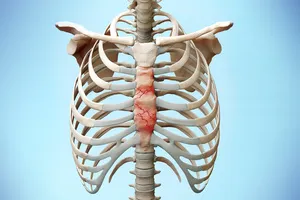

1. 늑골 연골염

늑골과 흉골을 연결하는 연골 부분에 염증이 생기면 늑골연골염이 발생합니다. 숨을 쉴 때마다 늑골이 움직이면서 염증 부위가 자극되어 통증이 심해지고, 가슴을 누르거나 압박하면 통증이 더욱 악화되는 것이 특징입니다. 충분한 휴식을 취하고, 진통 소염제를 복용하며, 물리치료를 병행하면 증상 완화에 도움이 될 수 있습니다.